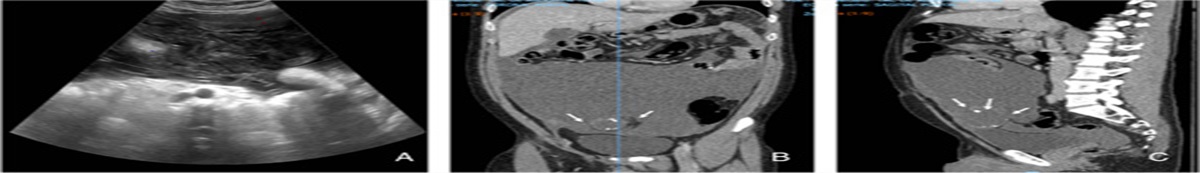

In July 2018, the patient had successfully delivered a term pregnancy without complications. The placenta was expelled but not sent for pathology review. After childbirth, on postpartum day 10, she experienced small amounts of vaginal bleeding that increased over the next few days. On postpartum day 40, the patient was transferred to the gynecological clinic. Physical examination showed an enlarged uterus (123×62 mm). Ultrasonography revealed an echogenic uterine mass (40×20×1.5 mm) with areas of necrosis and hemorrhage and hypervascular pattern on Doppler analysis. The blood hCG level was 500,000 mIU/mL. Compute tomography (CT) scan revealed solid nodular lesions (Fig. 1A) (>8) in both lungs, ranging from 10 to 22 mm in diameter. There was no evidence of brain or liver disease. In October 2018, the patient underwent biopsy of the uterine mass that confirmed the diagnosis of postpartum CCA. The patient was classified as having high-risk disease (stage III, score 9) based on FIGO staging and modified WHO risk-factor scoring system for gestational trophoblastic neoplasia. Therefore, first-line treatment with EMA-CO chemotherapy was given [Day 1: actinomycin-D 0.5 mg iv, etoposide 100 mg/m2 iv, methotrexate 300 mg/m2 iv. Day 2: actinomycin-D 0.5 mg iv, etoposide 100 mg/m2 iv, folinic acid 15 mg post 12 hourly for 4 doses. Day 8: vincristine 0.8 mg/m2 (maximum 2 mg), cyclophosphamide 600 mg/m2], starting October 2018. Unfortunately, after day 8 of first cycle, the patient developed severe abdominal pain and bowel obstruction caused by a volvulus, complicated by severe intestinal necrosis. She underwent bowel resection and complete hystero-annessectomy as emergency surgery. The procedure was performed by resident surgeon.

Figure 1Figure 1:

Comparison of pulmonary lesions. A, Lung computed tomography before chemotherapy. B, Lung computed tomography 3 months after chemotherapy. C, Lung computed tomography 5 months after chemotherapy.